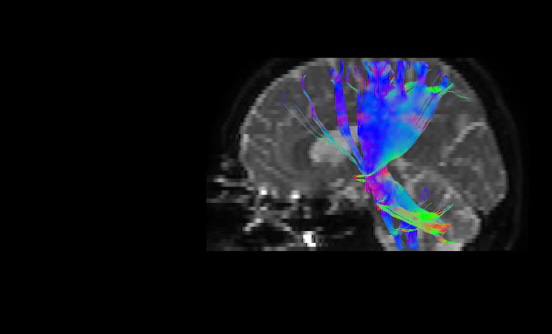

به گزارش پایگاه اطلاع‌رسانی دانشگاه عاوم پزشکی گیلان (وب‌دا)؛ دکتر ظهیر ریحانیان - رئیس مرکز آموزشی و درمانی پورسینا با اعلام این خبر گفت: اولین MRI پیشرفته به صورت DTI و MRS برای بیمار مبتلا به تومور مغزی در مرکز آموزشی و درمانی پورسینا انجام شد.

وی ادامه داد: سکانس‌های فوق برای تشخیص دقیق‌تر ضایعات مغزی و افتراق آن از سایر بیماری‌های مشابه کمک کننده می‌باشد همچنین در این شیوه نقشه برداری دقیق‌تر مغز برای انجام جراحی‌های پیشرفته بسیار حایز اهمیت است.